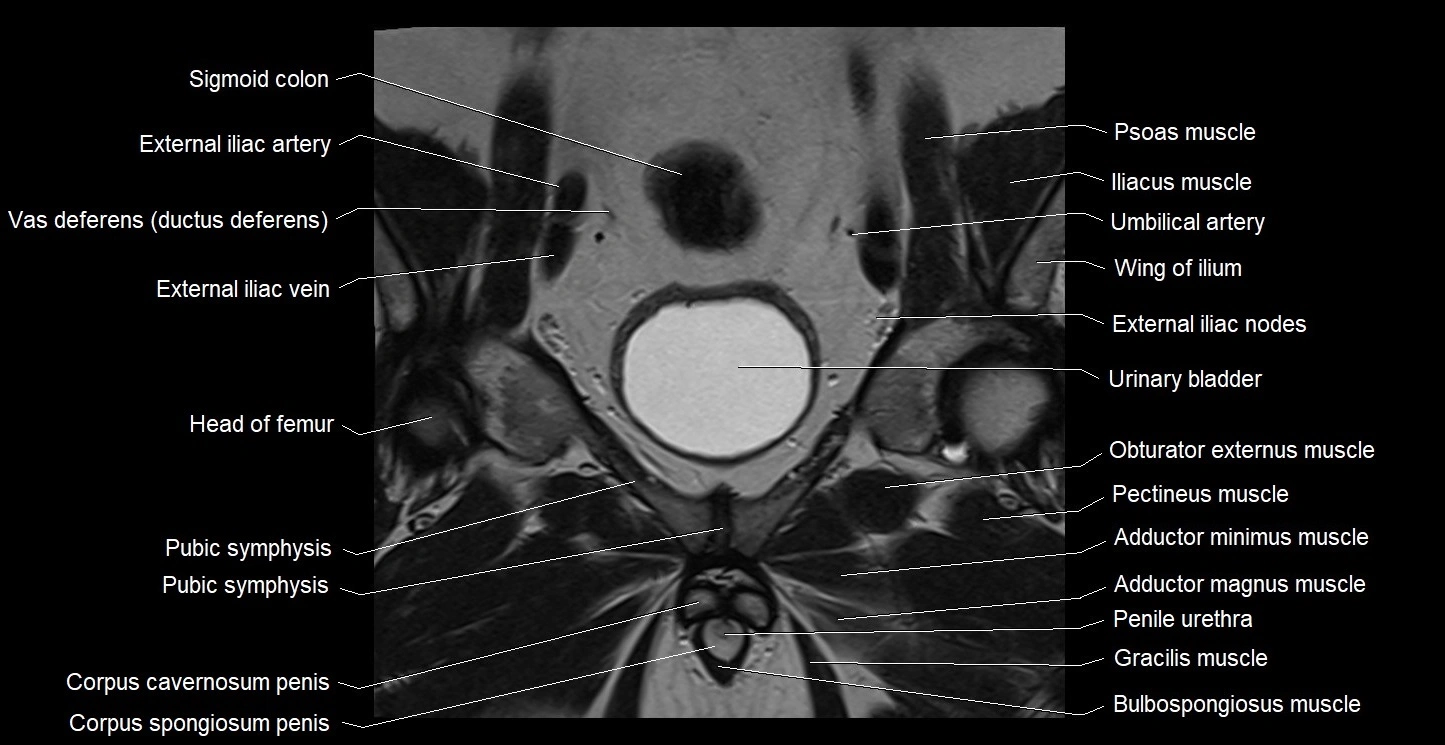

- Body of urinary bladder

- External iliac artery

- External iliac vein

- Gracilis muscle

- Head of femur

- Obturator externus muscle

- Pectineus muscle

- Penile urethra

- Pubic symphysis

- Sigmoid colon

- Umbilical artery

- Vas deferens